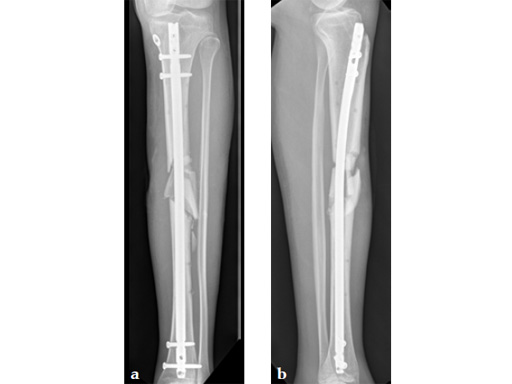

Case 2: Grade II open distal tibial fracture in a polytraumatized 52-year-old man.